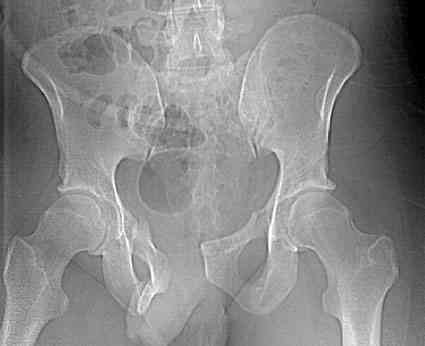

Уважаемые коллеги! опять вопрос по повреждению таза. Больной получил производственную травму 10 дней назад - удар балкой около 3 тонн в область верхней трети правого бедра и лона.

Был диагностирован перелом "типа бабочки" и повреждение уретры. Сделана цистостома. У насв отделении 3 дня. Имеется огромная флюктуирующая гематома с "галифе"-образной деформацией обеих бедер. Пнкционно эвакуировали в несколько приемов из подфасциальных полостей на бедрах около 3 литров геморрагического отделяемого с последующей эластической компрессией. При пункциях выявлено сообщение полостей на бедрах - видимо через поравннуюдиафрагму дна и полость таза - при удалении крови справа уменьшался объем левого бедра. Какой то активности проявялять покабоимся - аппаратная фиксация через отслоенные ткани представляется чреватой нагноением, открытая фиксация в условиях такой гематомы тоже не радует. Хотелось бы услышать ваше мнение

можно полечить в 2 этапа:как правило в области гребней гематомы все же не бывает, если гребни "свободны", то можно ограничиться на первом этапе передней рамой, вводя стержни через них (повреждение ротационно-нестабильное), затем после лечения отслаивающего повреждения Morel-Lavallee, выполнить открытую репозицию, внутреннюю фиксацию, возможно вместе с урологами. Тактику возможного лечения этой

18.12. - отдельное спасибо еще раз А.В.Рункову- больного оперировали (А.В.Рунков) - произведен остеосинтез аппаратом - фиксация за крылья, два стержня в лонные кости и репозиция (почти полная) снимки будут чуть позже.

Дренировали отслойки на бедрах с их санацией. В правой ягодичной области сформировалась зона некроза. Больной "подвешен" за аппарат.